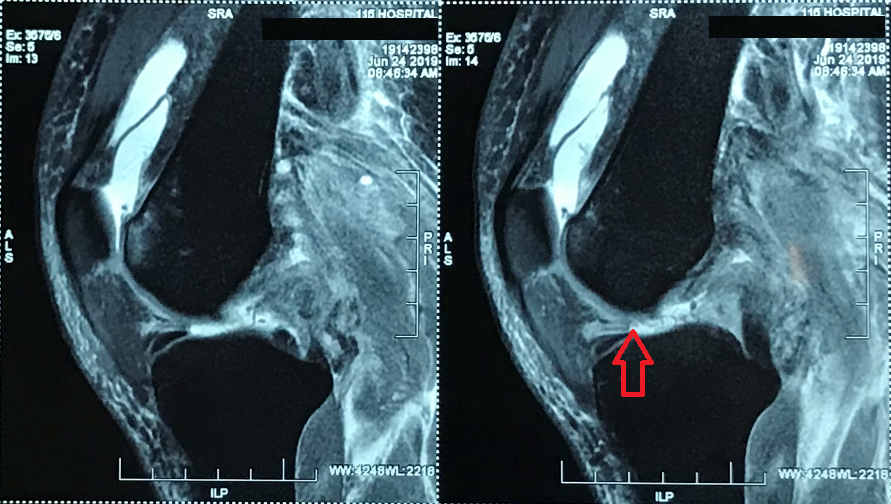

Tại khoa Điều trị theo yêu cầu – Y học thể thao, qua thăm khám bệnh nhân kết quả chụp MRI khớp gối trái cho thấy: Người bệnh bị đứt hoàn toàn đoạn gần dây chằng chéo trước (DCCT), đứt hoàn toàn đoạn gần dây chằng chéo sau (DCCS) và đứt hoàn toàn đoạn gần dây chằng bên bên ngoài.

Đồng thời người bệnh bị bong gân độ I dây chằng bên bên trong; không thấy tổn thương sụn chêm trong và ngoài, XQuang khớp gối trái bình thường.

| Hình ảnh phim chụp. |